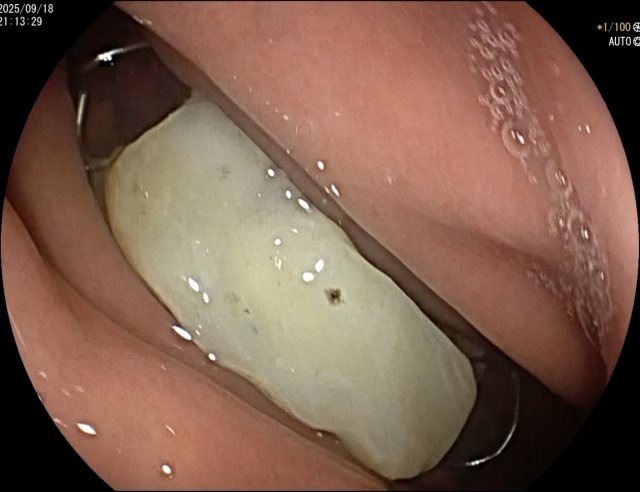

病例信息【患者信息】:男、16岁【主诉】:全身皮肤瘙痒伴皮疹10分钟【现病史及既往史】:10分钟前患者骑摩托车行驶途中,突感全身瘙痒,奇痒无比伴全身发热,心跳加快。急诊就诊,既往无类似病史,否认咽喉梗阻感、胸闷、气短、呼吸困难、恶心、呕吐、腹泻、乏力等不适。【检查】:血压:138/80mmHg,心率:116次/分,呼吸:21次/分。【临床诊断】:急性荨麻疹【治疗经过及结果】:给予吸氧、肌注扑尔敏1支,口服氯雷他定1片,静滴甲泼尼龙40mg后瘙痒明显减退,皮疹消失。病例讨论双手十指及双足未纹身,护士最后穿刺左手大拇指。